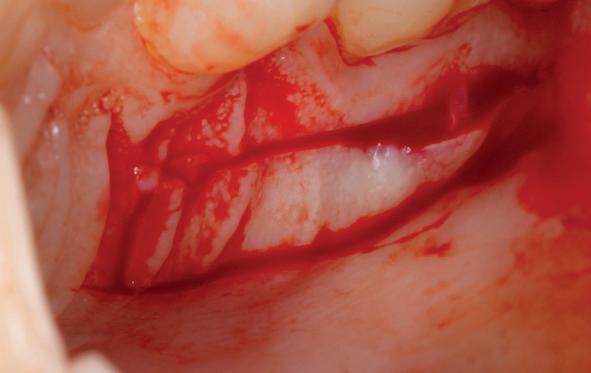

Voor de aanvulling zachte weefsels chirurgie werd gekozen voor de VISTA techniek, hierbij worden er twee incisies partial thickness flap hoog in de mucosa gemaakt, waarna er ruimte vanuit de incisies wordt getunneld tussen de gingiva en het periost door middel van VISTA tunnel instrumenten. Uit het palatum links werd een vrij gingivatransplantaat geoogst van 15x10 mm met een dikte van 3 mm, die voor inhechten werd geëpithelialiseerd. Als het epitheel niet wordt verwijderd, kan deze graft door

de mucosa heen groeien, dat ten koste gaat van de esthetiek. In het donorgebied wordt een collageen spons ingehecht, waardoor de patiënt daar minder last van heeft. Het bindweefsel wordt door de hul-

pincisies met hechtingen naar het buccale en coronale deel getrokken en aldaar ingehecht. Met twee incisies werd ook de emergence profile gecreëerd (afbeelding 6-13). Voor een goede genezing van het

7. Vervaardiging tunnel met tunnelinstrumenten

8. Geoogst bindweefseltransplantaat uit palatum